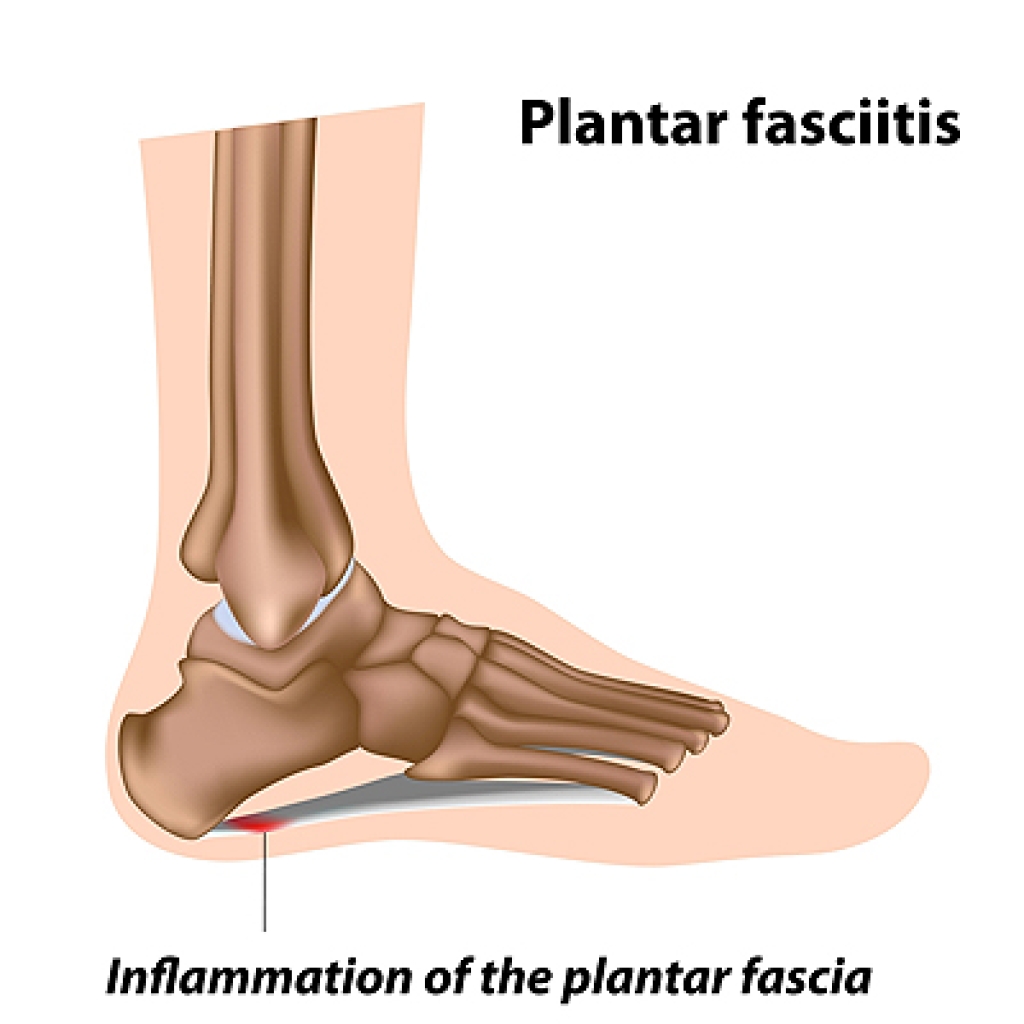

What Causes Plantar Fasciitis?

Plantar fasciitis is the most common source of heel pain. It occurs when the plantar fascia, the band of tissue running along the bottom of the foot that connects the heel to the toes, becomes inflamed. Plantar fasciitis is usually a result of repetitive overstretching of the plantar fascia. Common contributing factors include having high arches or flat feet, standing on hard surfaces for a long period of time, age (between 40 and 60), being overweight, wearing high heels, and a sudden change in activity level. Plantar fasciitis pain is most prevalent in the middle of the heel and it is usually worse after waking up in the morning or after taking a long rest. Patients who are experiencing heel pain should consult with a podiatrist for a proper diagnosis and to determine what route of treatment should be implemented.

Plantar fasciitis is the most common source of heel pain. It occurs when the plantar fascia, the band of tissue running along the bottom of the foot that connects the heel to the toes, becomes inflamed. Plantar fasciitis is usually a result of repetitive overstretching of the plantar fascia. Common contributing factors include having high arches or flat feet, standing on hard surfaces for a long period of time, age (between 40 and 60), being overweight, wearing high heels, and a sudden change in activity level. Plantar fasciitis pain is most prevalent in the middle of the heel and it is usually worse after waking up in the morning or after taking a long rest. Patients who are experiencing heel pain should consult with a podiatrist for a proper diagnosis and to determine what route of treatment should be implemented.

What Is Plantar Fasciitis?

Plantar fasciitis is one of the most common causes of heel pain. The plantar fascia is a ligament that connects your heel to the front of your foot. When this ligament becomes inflamed, plantar fasciitis is the result. If you have plantar fasciitis you will have a stabbing pain that usually occurs with your first steps in the morning. As the day progresses and you walk around more, this pain will start to disappear, but it will return after long periods of standing or sitting.

What Causes Plantar Fasciitis?

- Excessive running

- Having high arches in your feet

- Other foot issues such as flat feet

- Pregnancy (due to the sudden weight gain)

- Being on your feet very often

There are some risk factors that may make you more likely to develop plantar fasciitis compared to others. The condition most commonly affects adults between the ages of 40 and 60. It also tends to affect people who are obese because the extra pounds result in extra stress being placed on the plantar fascia.

Causes of Plantar Fasciitis

Plantar fasciitis, an inflammation of the tendon that runs along the bottom of the foot, is the most common cause of heel pain. This condition can develop following long hours of standing, walking, running, or participating in sports. In rarer cases, an acute injury to the bottom of the foot can damage the plantar fascia and bring forth early stages of this condition. Having flat or overpronated feet, high arches, wearing ill-fitting and uncomfortable shoes, having tight calf muscles, or being overweight or obese can also cause plantar fasciitis. If you are suffering from heel pain, it is strongly suggested that you schedule an appointment with a podiatrist near you.

Plantar fasciitis, an inflammation of the tendon that runs along the bottom of the foot, is the most common cause of heel pain. This condition can develop following long hours of standing, walking, running, or participating in sports. In rarer cases, an acute injury to the bottom of the foot can damage the plantar fascia and bring forth early stages of this condition. Having flat or overpronated feet, high arches, wearing ill-fitting and uncomfortable shoes, having tight calf muscles, or being overweight or obese can also cause plantar fasciitis. If you are suffering from heel pain, it is strongly suggested that you schedule an appointment with a podiatrist near you.